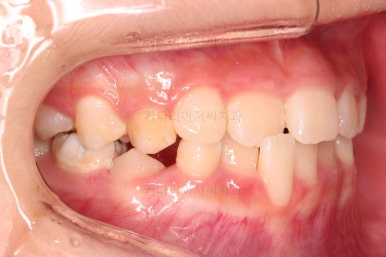

바로 전후 비교사진 올립니다.

골격의 문제가 없었고 골격에 대한 치료가 아니었지만 얼굴 모습도 약간의변화가 있죠?

함몰감이 약간 있던 윗입술 부분이 볼륨감이 생기면서 자연스러운 아이얼굴 비율이 되었어요.

치열도 자연스럽게 예뻐졌네요.

3개월만에요😄

이 후에 프리올소라는 장치로 유지과정 중입니다.

치료를 프리올소로 한건 아니지만 장기적으로 재발의 요인이 몇 가지 관찰되어 유지장치 겸 해서 사용 중이죠.